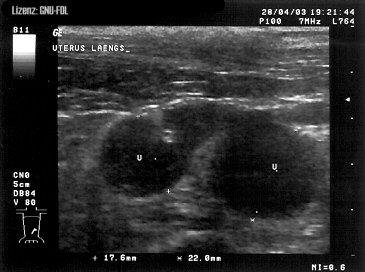

Quelle:https://de.wikipedia.org/wiki/Datei:Pyometra_Sono.jpg

Pyometra beim Hund. Mit U gekennzeichnet sind

zwei Uterusschlingen, welche vom Schallkegel quer

angeschnitten wurden.